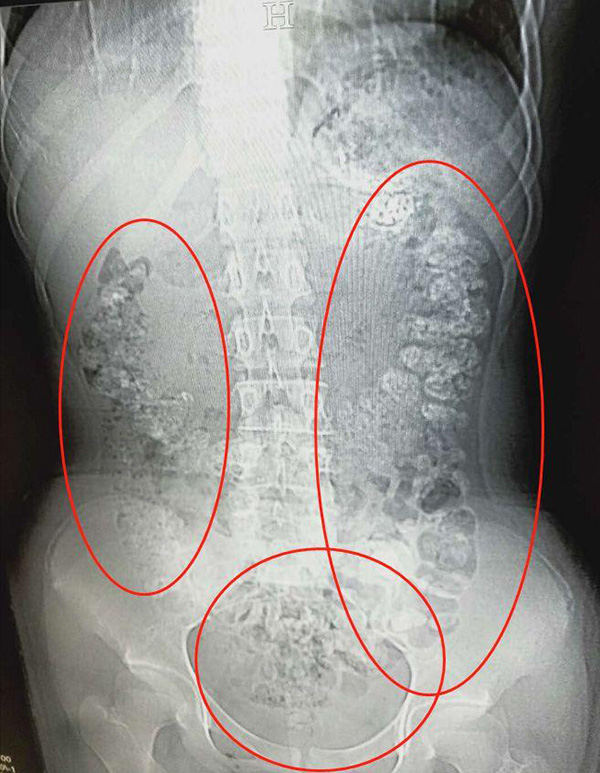

5月28日晚,浙江的小姑娘小沈(化名)在父母陪同下到浙江诸暨市人民医院急诊,说自己五天都没有排便,还肚子疼,也吃不下东西。医生见她肚子鼓鼓的,便安排了腹部CT,检查结果让医生大吃一惊:患者胃部、横结肠、升结肠、降结肠、乙状结肠,一直到肛门,全是一颗颗,圆圆的高密度阴影,看上起起码要百余颗——全都是没有消化的"珍珠”

经过问诊,女孩说5天前喝过珍珠奶茶,随后医生给患者开了润肠通便的药物,帮助将未消化的"珍珠"排出体外。